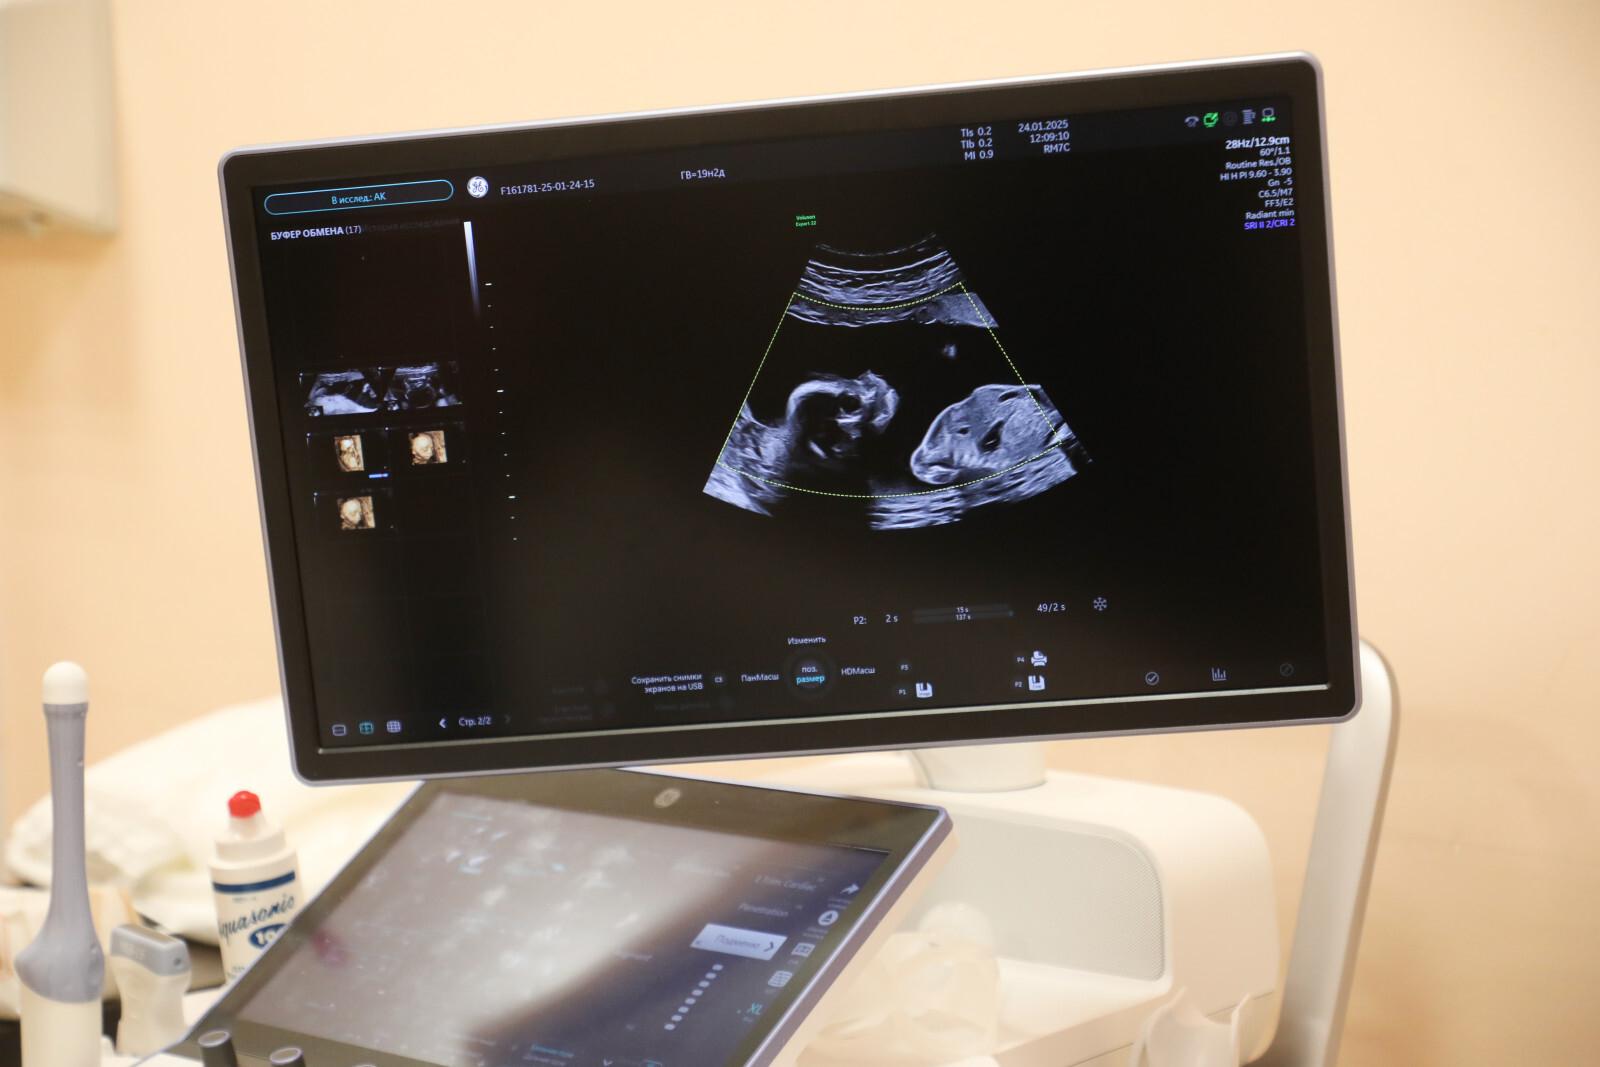

В Петербурге стартовала Неделя ответственного отношения к беременности

В Петербурге началась Неделя ответственного отношения к беременности. В ее рамках жителям репродуктивного возраста от 18 до 49 лет в Комздраве города напомнили о возможности проверить репродуктивное здоровье в ходе расширенной диспансеризации.

В настоящее время в Петербурге работают 20 учреждений родовспоможения. Кроме того, помощь пациенткам оказывают 47 женских консультаций и 3 акушерско-гинекологических отделения государственных поликлиник.